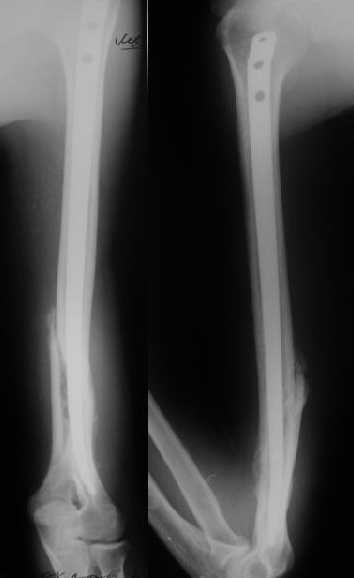

Мы в последние годы все еще используем для переломов такой локализации эластичные титановые стержни (по мотивам ярославских разработок, Зверева-Ключевского). Такой стержень можно вводить не через сухожилие надостной мышцы, а дистальнее.

Снимки до, через 1 и 2 мес. после синтеза.